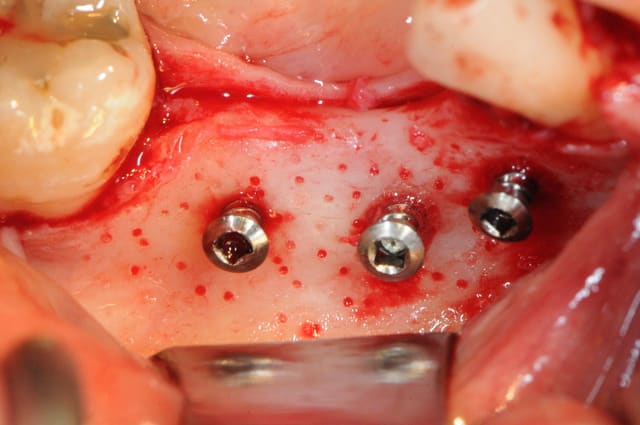

4 après ouverture

7-8: et voilà 3 vis qui vont maintenir ma membrane au dessus de l'os.

9-10-11: la membrane maintenue par deux pins sur la table interne osseuse, comblement osseux recouvrant les têtes des vis puis je rabat la membrane que je fixe sur la table osseuse externe